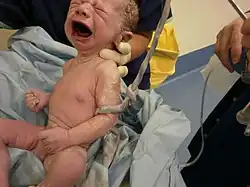

Umbilical cord of a three-minute-old baby. A medical clamp has been applied. | |

A newborn at 45 seconds, with umbilical cord clamped.

A newborn at 45 seconds, with umbilical cord clamped. -